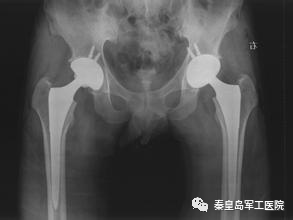

股骨头坏死人工关节置换术前及术后X线片